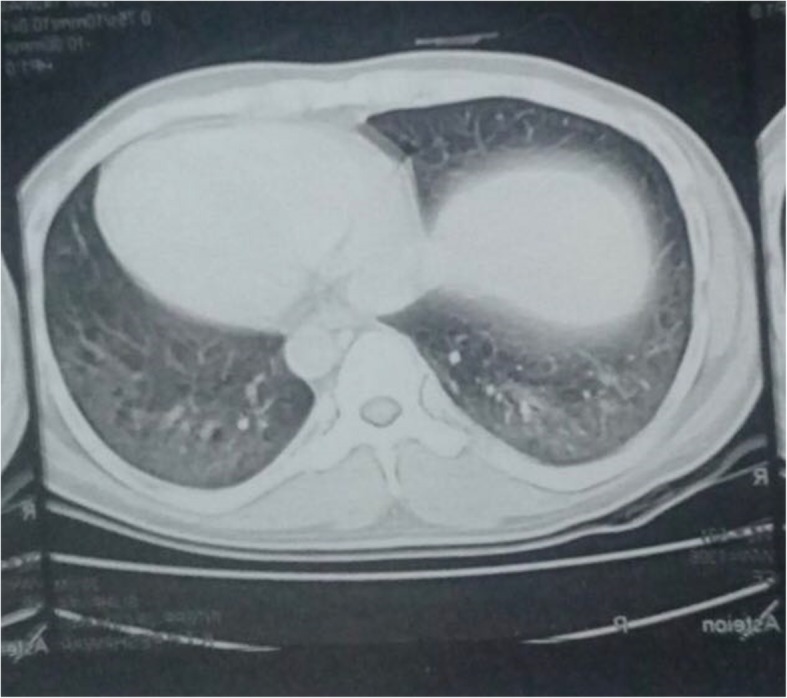

A 27-year-old Pakistani, Asian man, a medical student, with no previous comorbidities and no past history of tobacco smoking and alcohol intake, presented with 3 months’ history of frequent bouts of lower respiratory tract infections associated with exertional dyspnea, arthralgias, gradual weight loss, low grade fever, easy fatigability, and anorexia. His family history was also insignificant for any respiratory or other systemic pathology. In the fourth month of his illness, his fever became high grade associated with profuse sweating. All the baseline investigations were carried out on an out-patient basis. His white cell count was raised and a chest X-ray showed basal consolidation. A suspicion of pneumonia was made and he was started on broad-spectrum antibiotics. His condition improved temporarily but the symptoms re-emerged after a few days. He also received a course of orally administered fluoroquinolones but there was no improvement. A subsequent high resolution computed tomography (HRCT) scan of his chest revealed bilateral ground-glass haziness with areas of traction bronchiectasis, more so in the posterior basal segments of both lower lobes, suggestive of ILD (Figs. 1 and 2). He was given dexamethasone which improved his respiratory symptoms. In the sixth month of illness, he developed progressive proximal muscle weakness. He had difficulty in rising up from a chair and had difficulty in rising up from a squatting position. Throughout this period he had progressive weight loss (19 kg lost in 2 months) and profuse sweating. He was admitted to our hospital and thoroughly investigated. With time his proximal muscle weakness became severe and defined. It now involved his upper limbs as well and he had difficulty in combing his hair. He also gave a history of painful and cyanosed finger tips in winter.

Fig. 2.

CT scan showing areas of ground glass haze and traction bronchiectasis